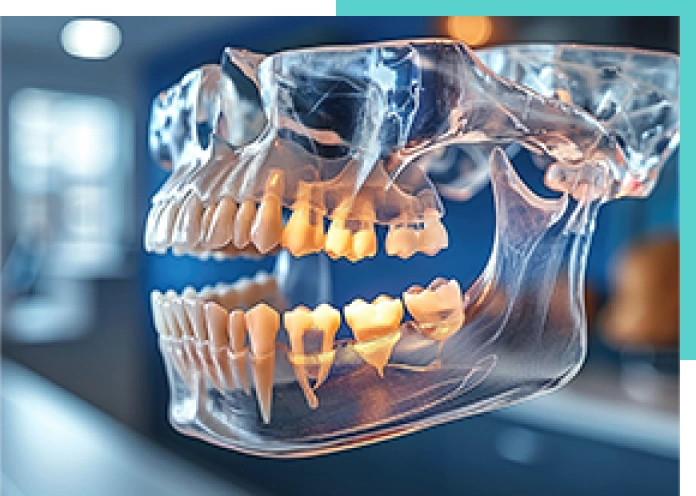

通常の口:笑顔の状態でも歯茎は見えにくい ガミースマイルのお口:唇の位置が上がりすぎている、歯列の位置が下すぎるor前すぎる、歯が短すぎる

ガミースマイルとは、笑った時に口元から歯ぐき(歯肉)が見えてしまう状態のことです。この症状があると口元の美しさが損なわれてしまうことがあります。

キレイな白い歯であれば、口元が美しくみえると思われがちですが、実は笑った時の歯ぐきの見え方や歯の形や大きさも、口元の美しさを創る重要な要素となります。